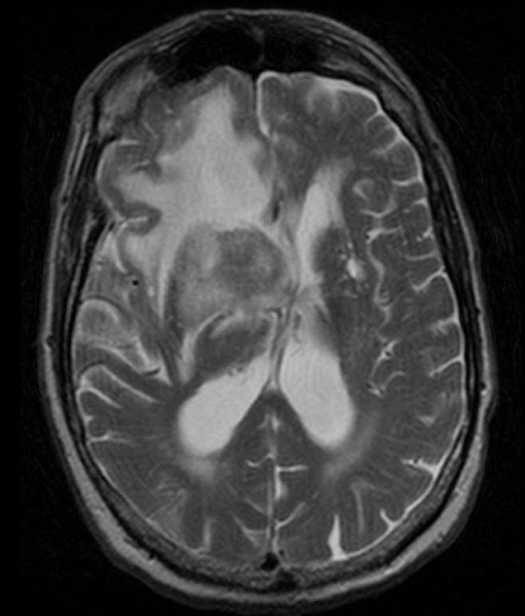

2. Medulloblastoma

- Origin: Neuroectodermal (germ cell-derived)

- Location: 4th ventricle, cerebellum

- Features:

- Obstructive hydrocephalus: morning headache, vomiting

- Gait instability, diplopia, cerebellar signs

- Treatment: Surgical resection + radiation + chemotherapy

- Prognosis: Poor (70% 5-year survival; CSF spread common)